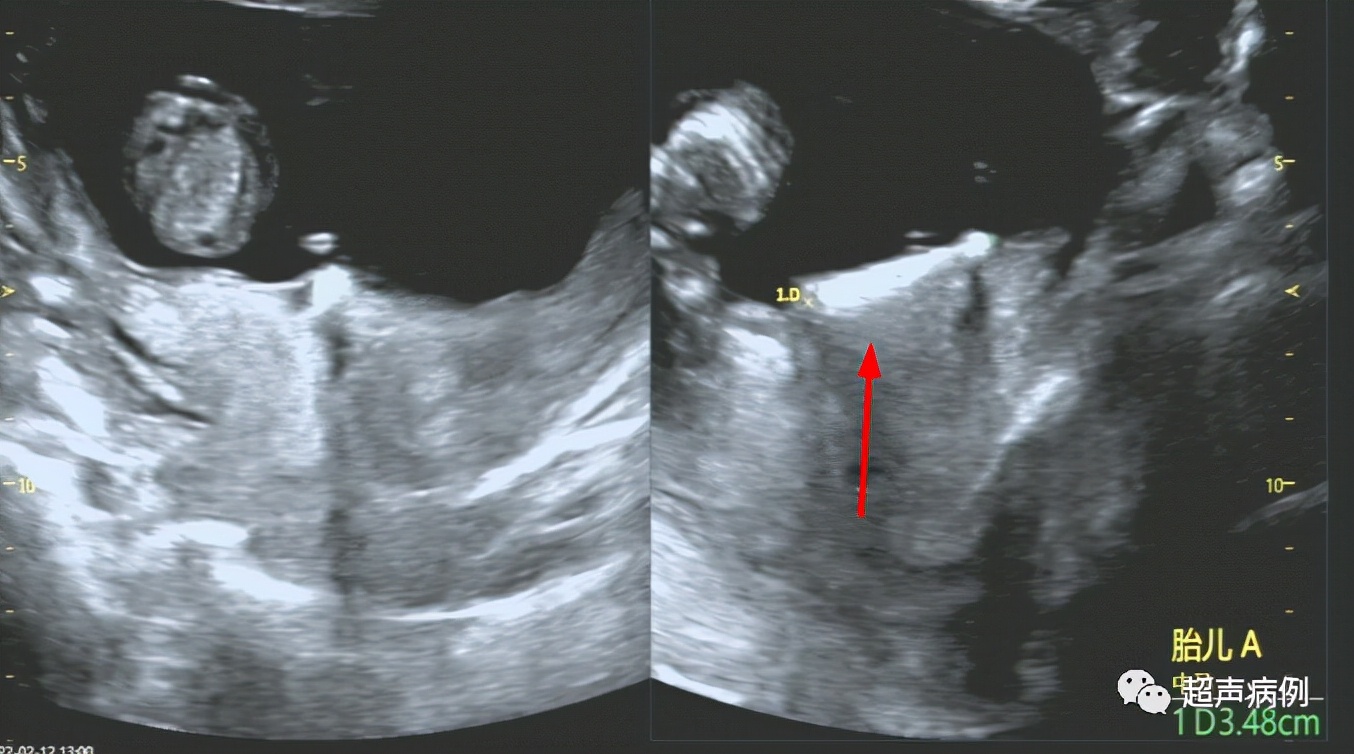

此时我的设备远场增益很强,调整增益后,终于在孕妇子宫前壁下段与胎膜之间发现了节育器。